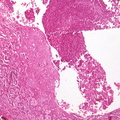

HISTOLOGY: RESPIRATORY: Lung: Carcinoma: Micro H&E low mag squamous cell carcinoma in dense fibrous stroma same case as 6